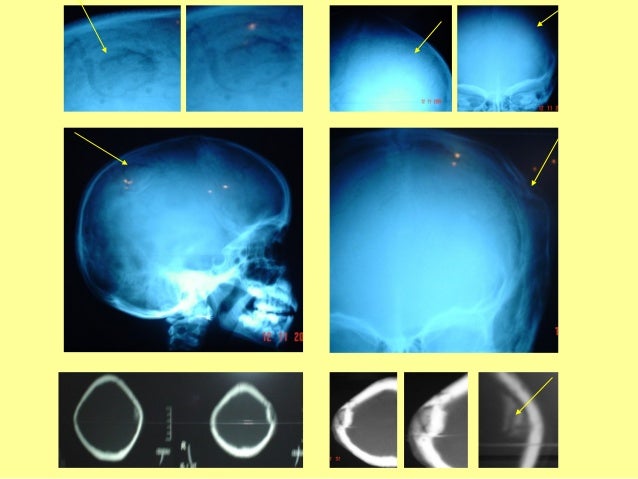

34. 34. FRACTURAEXPUESTADECRÁNEO

35. 35. RX CRÁNEO PERFILRX CRÁNEO PERFIL RX CRÁNEO FRENTERX CRÁNEO FRENTENEUMOVENTRICULOGRAFIANEUMOVENTRICULOGRAFIAPOSTRAUMÁTICAPOSTRAUMÁTICA